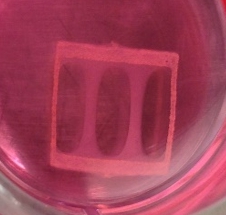

Two lab-grown human muscle bundles stretched in a rectangular frame submerged in a medium. (Credit: Duke University)

They expanded these “myogenic precursors” by more than a 1000-fold, and then put them into a supportive, 3D scaffolding (support structure) filled with a nourishing gel that allowed them to form aligned and functioning muscle fibers.

“We have a lot of experience making bioartifical muscles from animal cells in the laboratory, and it still took us a year of adjusting variables like cell and gel density and optimizing the culture matrix and media to make this work with human muscle cells,” said Madden.